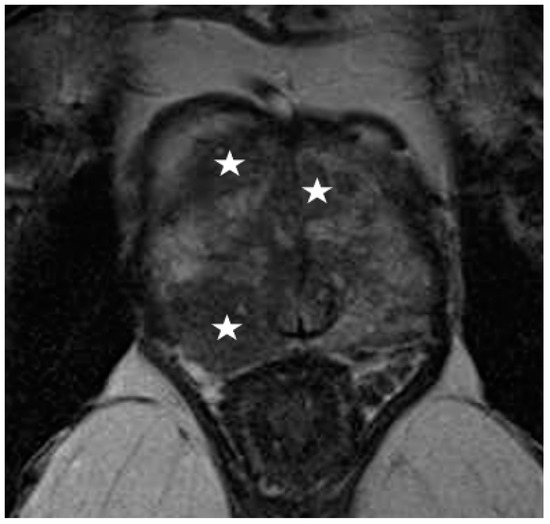

2.5.1. EPE Prediction